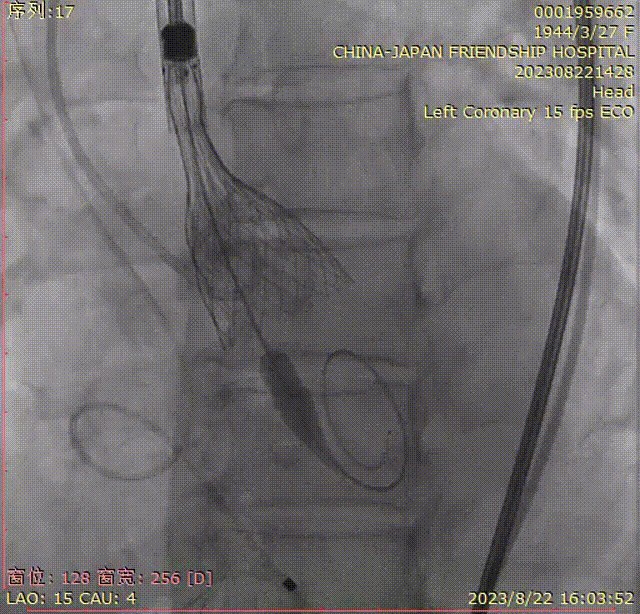

回撤脑保护装置,完成手术。

特别值得一提的是,团队在两个脑保护装置中都发现了栓子的掉落。这一发现表明SENTINEL可以成功地捕捉到手术操作过程中产生的碎片,从而有效地避免了脑卒中的发生。

【可见脑保护装置捕获碎片】